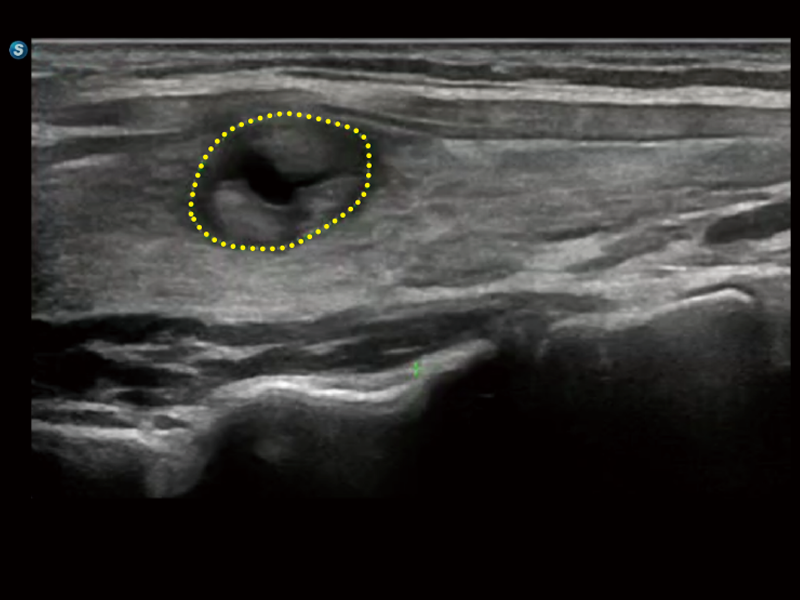

通過創(chuàng)新的Matrix E自適應(yīng)濾波算法,能有效濾除軟組織和噪聲信號(hào),最大限度保留超低速微細(xì)血流的信號(hào);結(jié)合超長(zhǎng)時(shí)間域算法,極大提升細(xì)微血流的敏感性和空間分辨率,更真實(shí)的反應(yīng)組織、包塊的血流灌注情況。